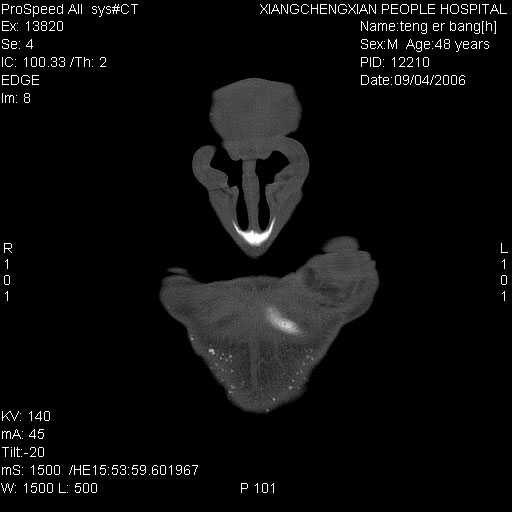

患者,男,以头面部外伤后头疼1小时为主诉入院,患者1小时前被他人打伤头部及左侧面部,眼睑无水肿,左侧面部肿胀压疼,未触及骨擦音。专科检查:耳鼻喉未见异常。

ct:平扫+冠扫:双侧鼻骨对比,冠扫s6#示右侧鼻骨尖部可见线状低密度影,边缘光滑,并见硬化.软组织未见肿胀.

诊断意见:鼻额缝(鼻骨与上颌骨额突缝),但个别同志认为是骨折.因此请同行们会诊.多谢了!